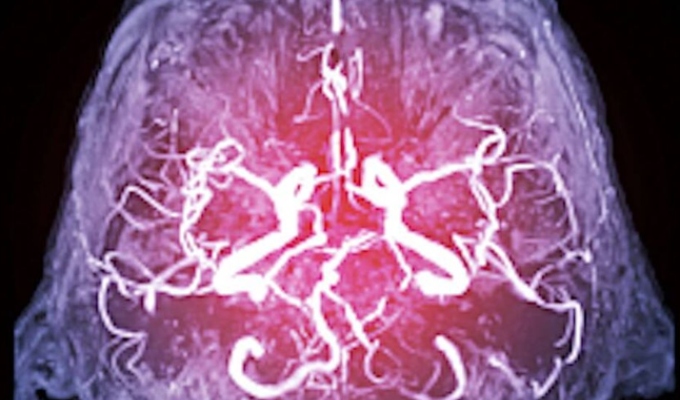

Este fenómeno, que los científicos llaman “priorización gradual”, implica que el cerebro selecciona y refuerza la información con base en su conexión con un hecho emocional. En este proceso intervienen de forma decisiva el hipocampo, la amígdala y la neocorteza, regiones cerebrales relacionadas con la memoria, las emociones y el aprendizaje.